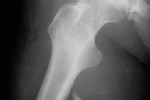

Frattura ossea Per frattura ossea o infrazione si intende la rottura traumatica o spontanea di un osso dello scheletro. Avviene quando la forza meccanica eccede la resistenza dell'osso che generalmente quando quest'ultimo è sano è molto elevata. In... ...